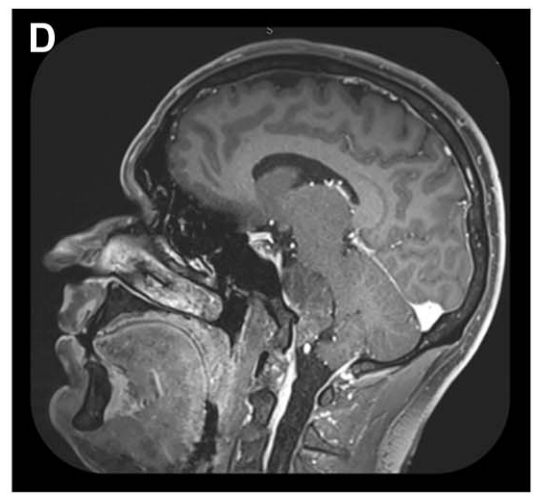

MRI检查显示诺亚术前栓塞后3D-CISS序列多平面重建MRI,可见脑膜瘤与神经血管结构存在复杂关系。

矢状位MRI显示肿瘤经栓塞后血供部分阻断(部分去血管化)。